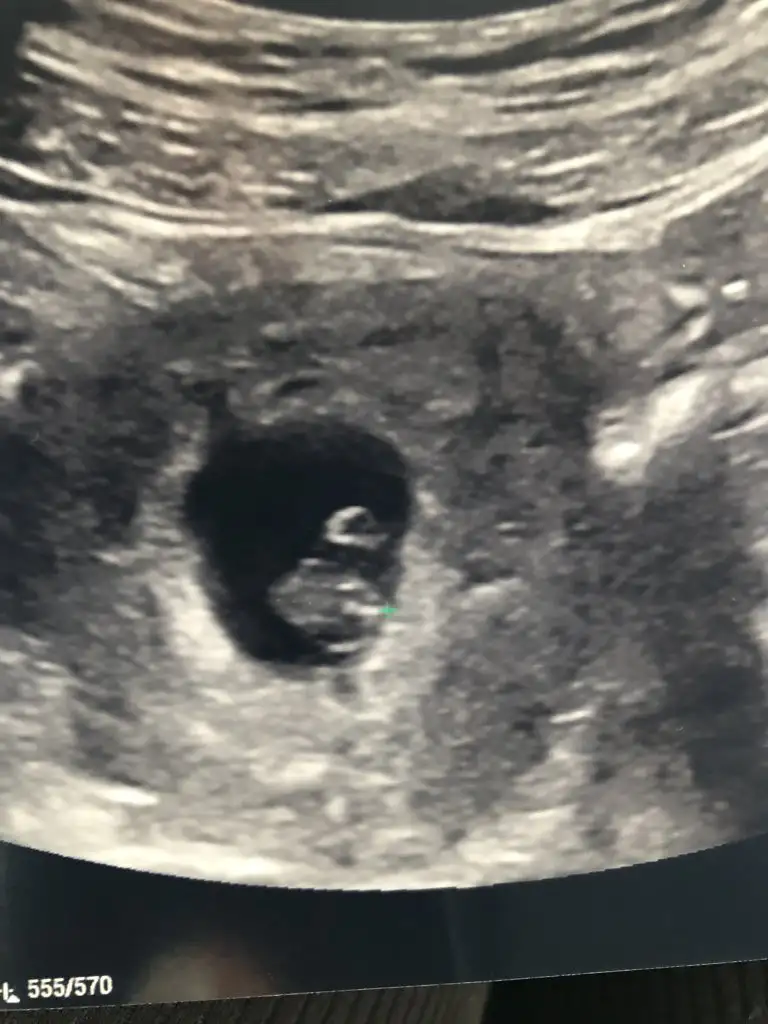

7 haftadayiz 6+6 dayız çok şükürBelli olmaz benim bir tanıdık 12 yıl sonra kendiliğinden hamile kaldı mucize bebek dersin vakti şimdi dersinsizin kaç haftalıktı bebişiniz

Benim 6+37 haftadayiz 6+6 dayız çok şükür

Çok şükür 7+3 günlük dedi 1.18 cmAz kaldı geldi vakit son yarım saat

Maşallah canım. Senin transferin ne zamandıÇok şükür 7+3 günlük dedi 1.18 cm

Sağol canım doktor 7 haftalık bu kız dediAY yavrum benim Allah sağlıkla doğmalarını nasip etsin ben şimdi cinsiyetlerini merek etmeye başladım. hadi gözün aydın canım